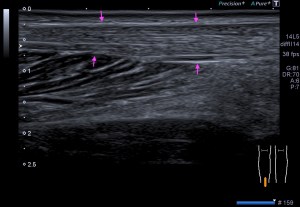

La radiografía revela aumento de las partes y se refrenda en la ecografía como puedes ver en la imagen aunque aún no hay afectación en el hueso en el caso que te presento hoy.

Ecografícamente y debido a su levedad, en el caso de hoy solo observamos cambios en las partes blandas de la cara lateral de la cabeza del quinto metatarsiano, este tejido se muestra heterogéneo, la cortical del hueso ligeramente prominente sin afectación de la misma.